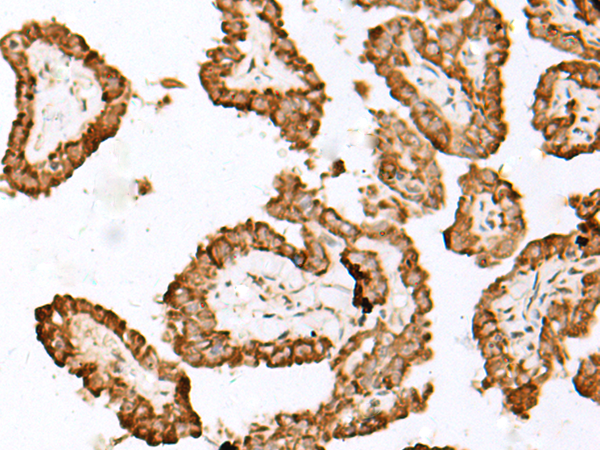

分类: 科研抗体货号: P04417别名: PD1, PD-1, CD279, SLEB2, hPD-1, hPD-l应用: IHC反应种属: Human